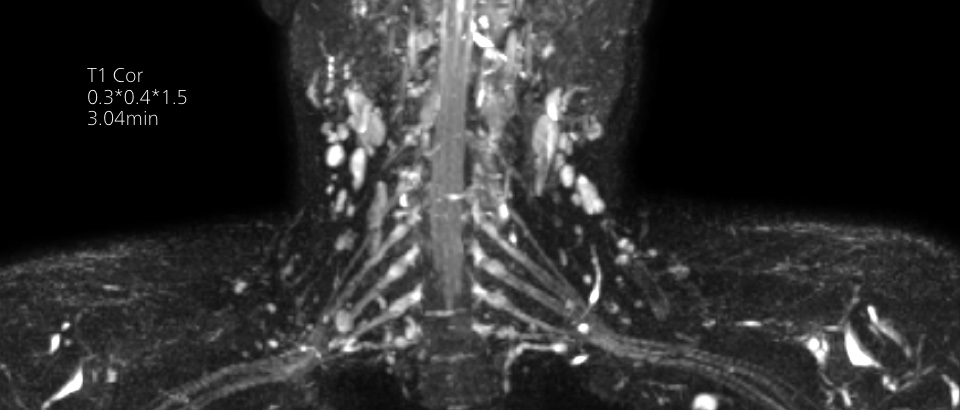

Philips Breezeコイルは、あらゆる解剖学的構造に対して一貫した高品質の画像を取得する汎用性を備えています。

Philips Breezeコイルは、正確な解剖学的構造や非常に小さな関節を撮影するための優れた汎用性を備えています。最大55 cmの広い撮像視野と優れたSNRにより、高い画質が得られます。